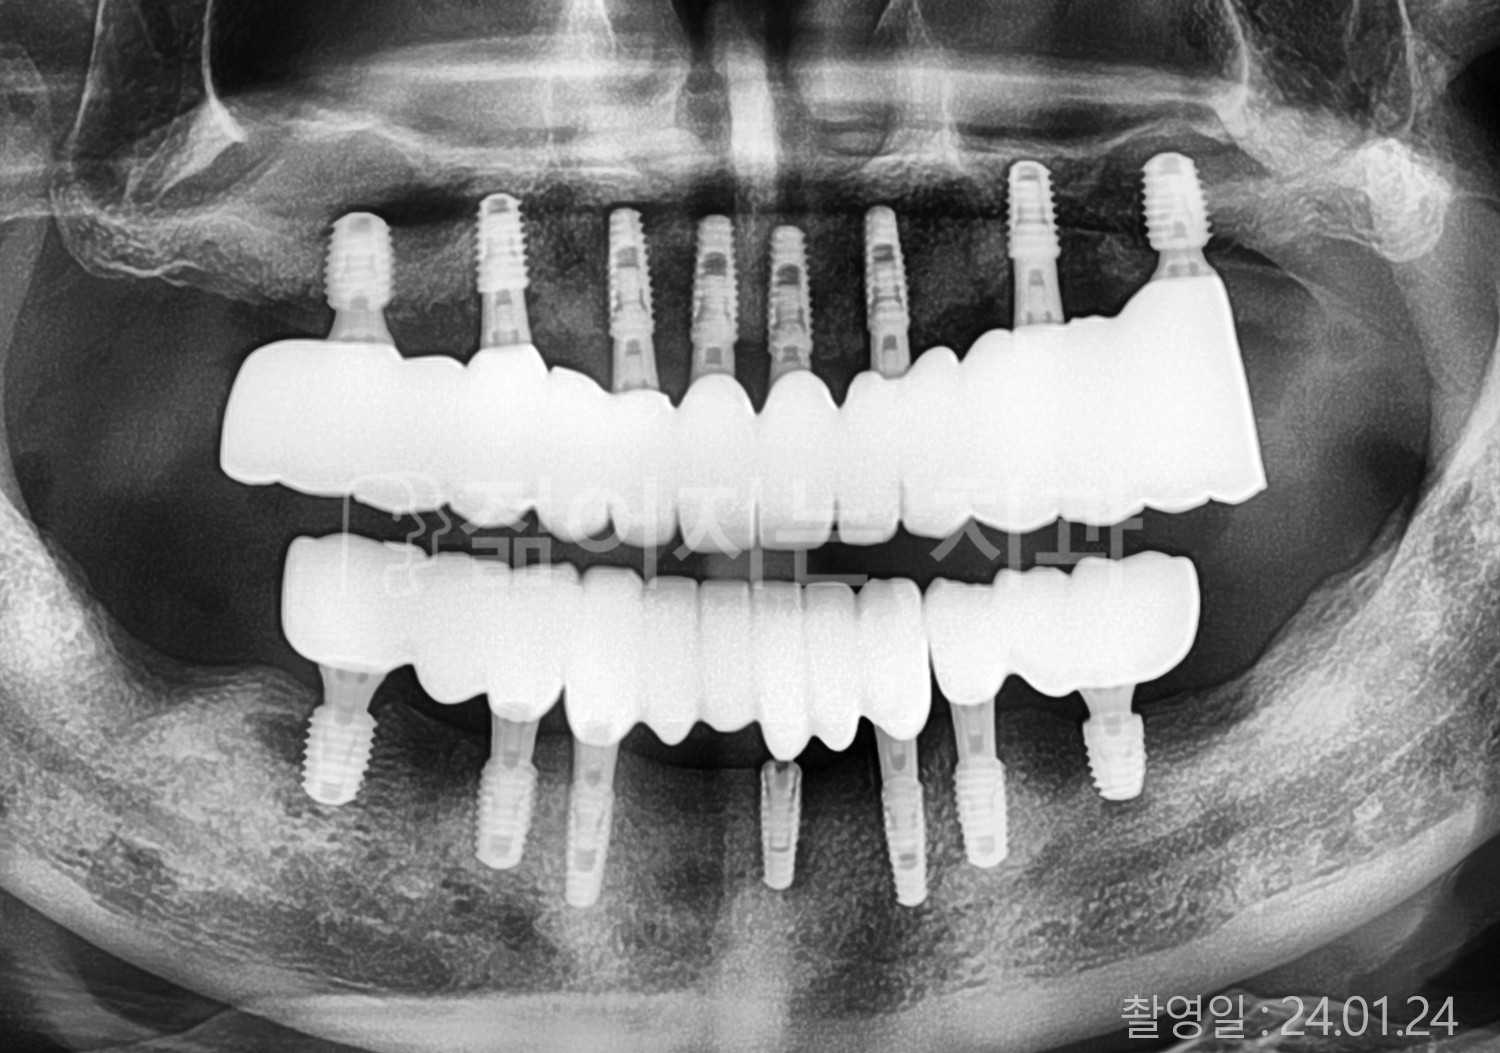

• 60대 전체치아 10개 이상 임플란트